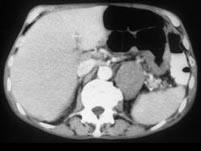

问题 男,57岁,腹部隐痛不适伴低热2月余,腋下可触及数个肿大的淋巴结,请结合图像,作出诊断 ( )

选项 A、左侧肾上腺腺瘤 B、左侧肾上腺转移瘤 C、左侧恶性嗜铬细胞瘤侵及胃脾 D、左侧肾上腺淋巴瘤且胃脾受累 E、左侧肾上腺癌并胃脾转移

答案 D